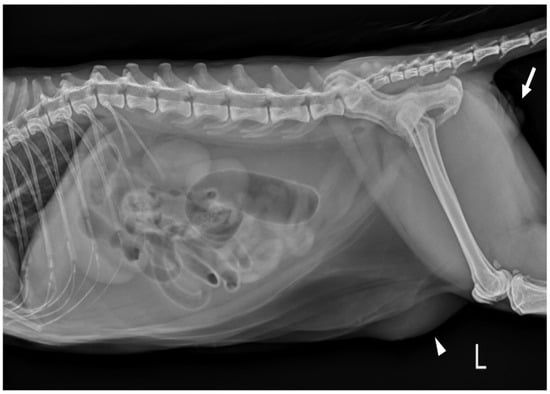

Complete blood count (CBC) was normal except for mild lymphopenia (1.24 × 109 cells/L) (reference interval [RI]: 2–7.2) and mild eosinopenia (0.12 × 109 cells/L) (RI: 0.3–0.7). Serum electrolyte concentration, serum biochemistry, gas analysis, and total T4 revealed no abnormalities except for elevated Feline serum amyloid A (FSAA) level (23 μL/mL) (RI: 0–10) and mild hyperglycemia (171 mg/dL) (RI: 73–134). Urethral catheterization revealed complete patency. Urinary samples collected by ultrasound-guided cystocentesis showed no abnormal laboratory urine test results and a negative result on bacterial culture. Abdominal radiography (XPLRER-900, Medien International Co. Ltd., Anyang, Korea) revealed edema of the perineal region. A cutaneous mass with fat opacity was also detected in the inguinal regions; this was later suspected to be a lipoma (Figure 2). Ultrasonography performed using Philips iU22 SonoCT system (Philips Ultrasound, Bothell, WA, USA) revealed that the erect, swollen penis’s parenchyma was homogenous and hyperechoic. The penile cavernosal artery was not clearly identified by color-flow Doppler ultrasonography with the lowest Nyquist limit range of −2.5–2.5 cm/s (Figure 3). Ultrasound-guided fine needle aspiration of the left inguinal mass identified lipid droplets before staining, and single large clusters of well-differentiated adipocytes with Diff-Quick staining were observed under a microscope.

Figure 2. Left lateral abdominal radiograph in a cat revealed edema of the perineal region (white arrows). The cutaneous mass with fat opacity in the inguinal region (white arrowheads) was cytologically suspected as a lipoma.